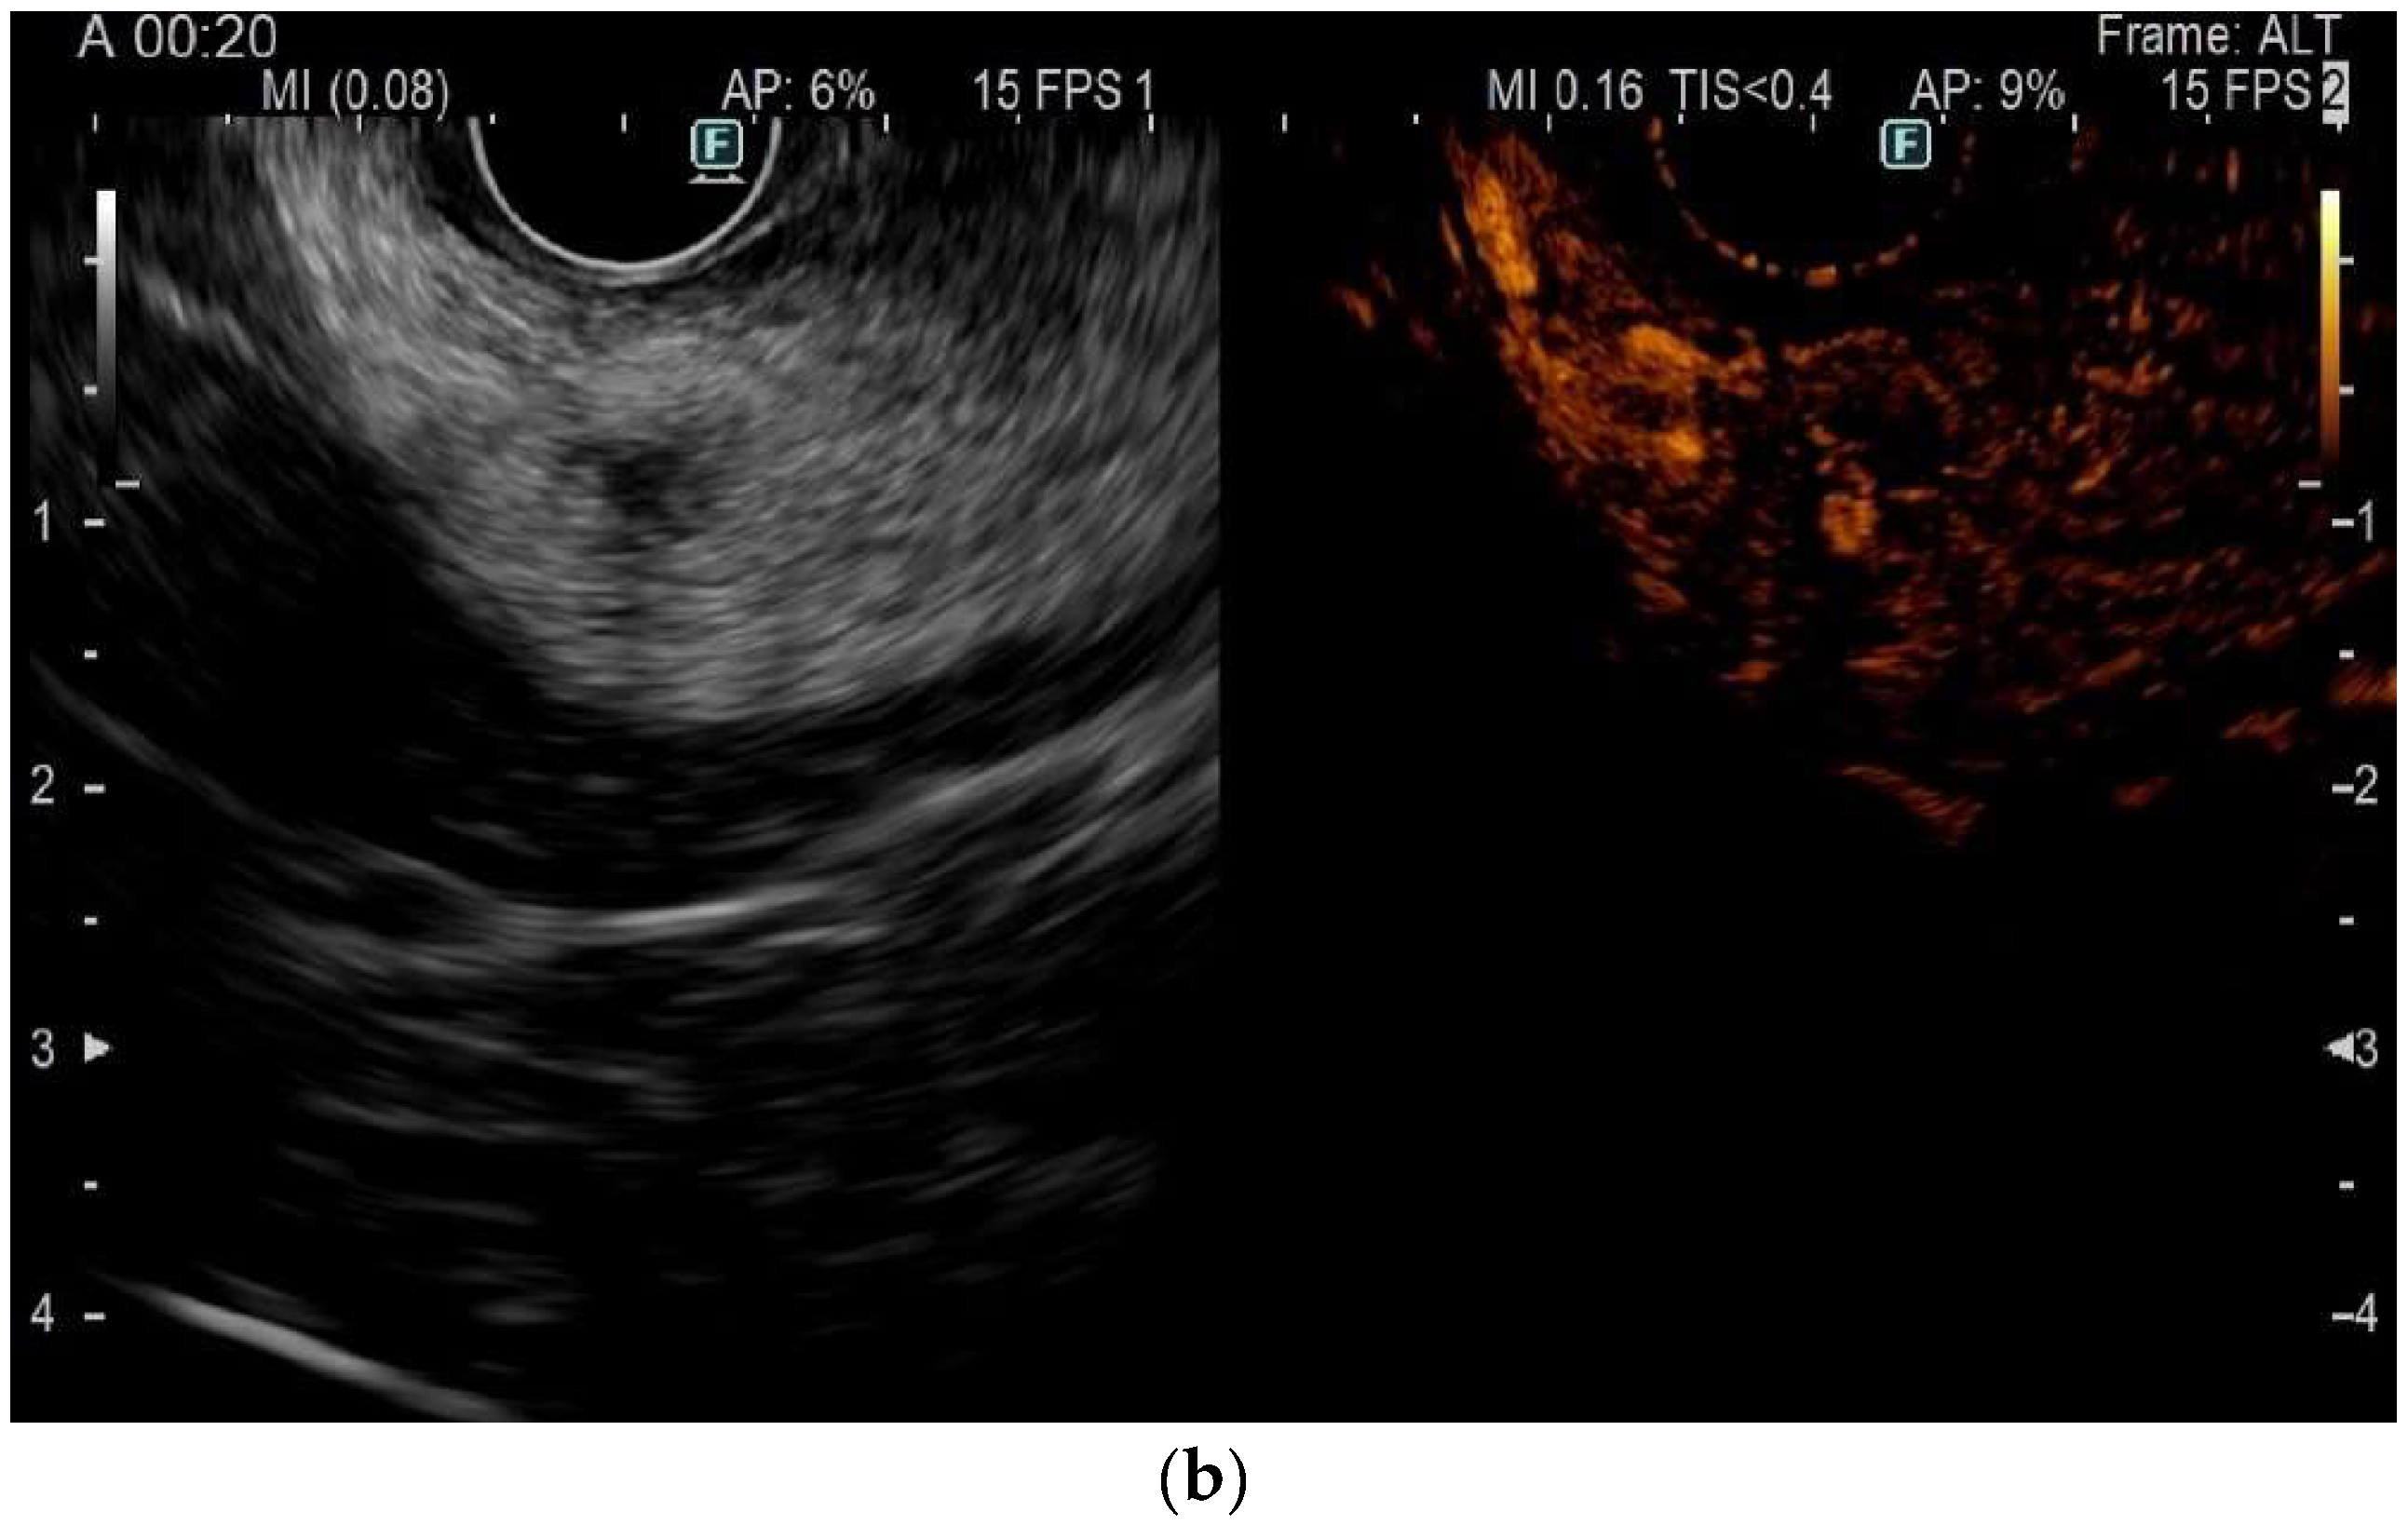

3.3. Role of Contrast Harmonic EUS (CH-EUS) and Follow-Up

- Choi, J.-H.; Seo, D.-W.; Song, T.J.; Park, D.H.; Lee, S.S.; Lee, S.K.; Kim, M.-H. Utility of Contrast-Enhanced Harmonic Endoscopic Ultrasound for the Guidance and Monitoring of Endoscopic Radiofrequency Ablation. Gut Liver 2020, 14, 826–832. [Google Scholar] [CrossRef]